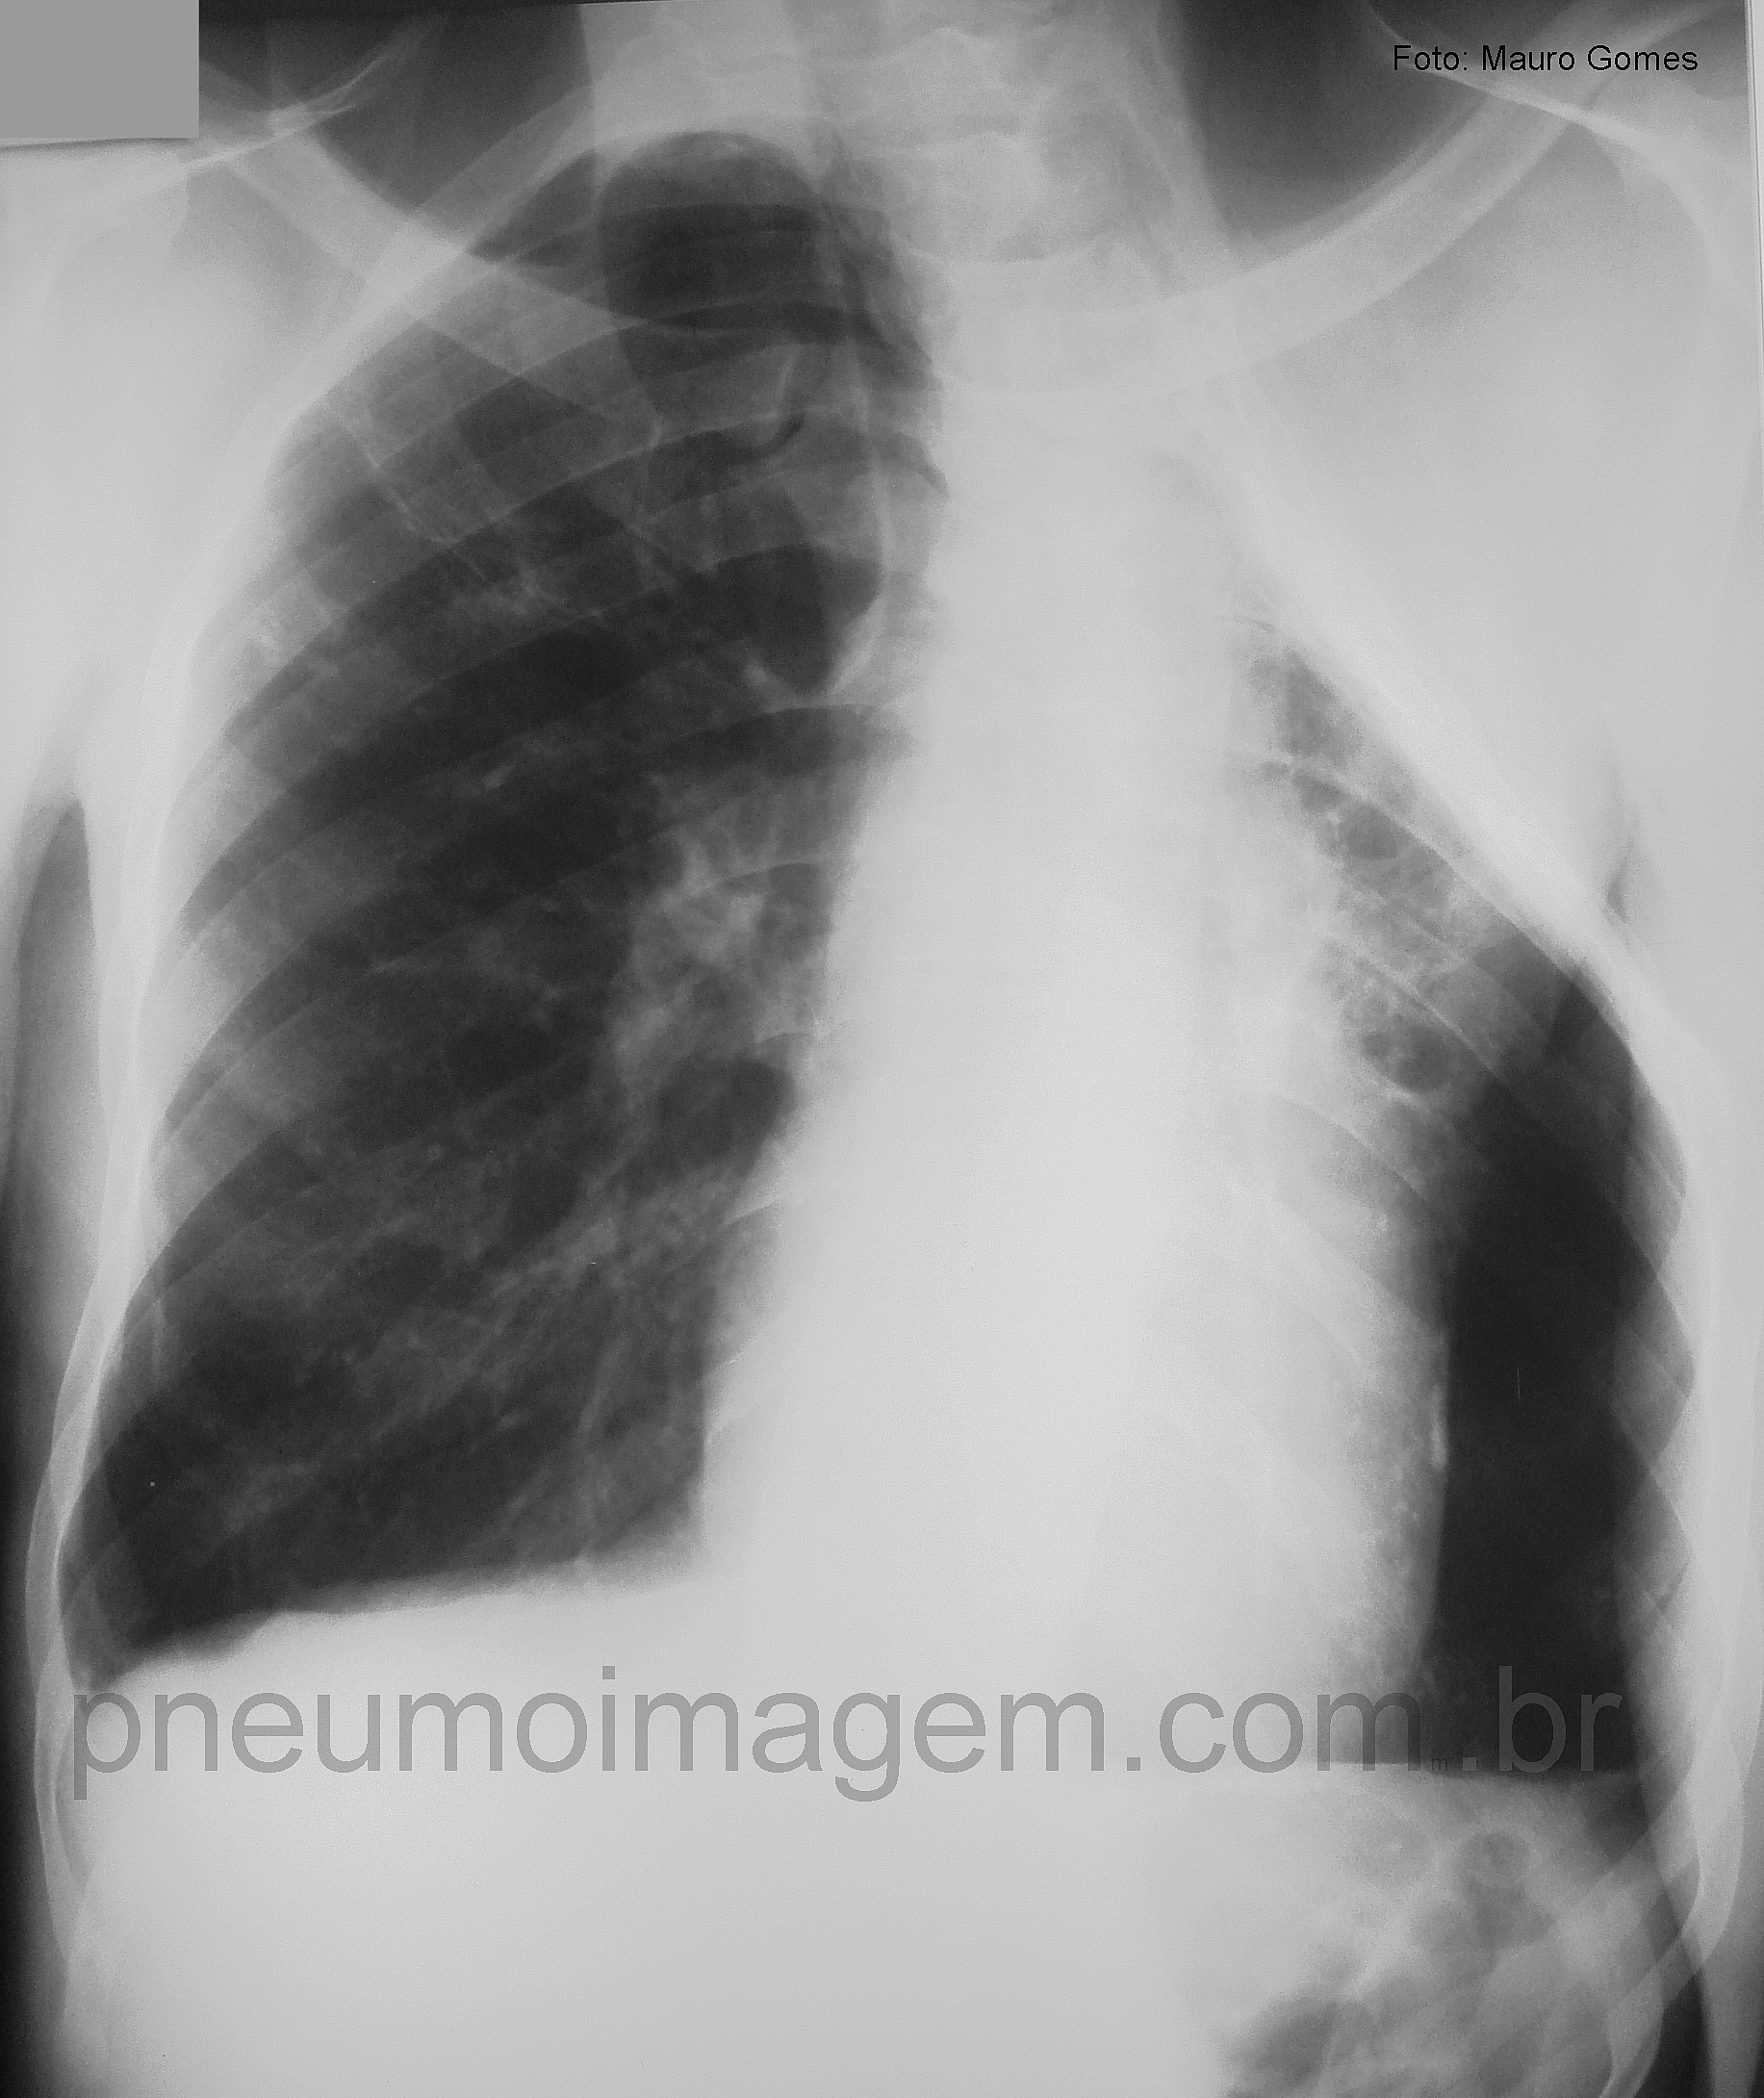

Veja imagens de Tuberculose no PneumoImagem, clique aqui.